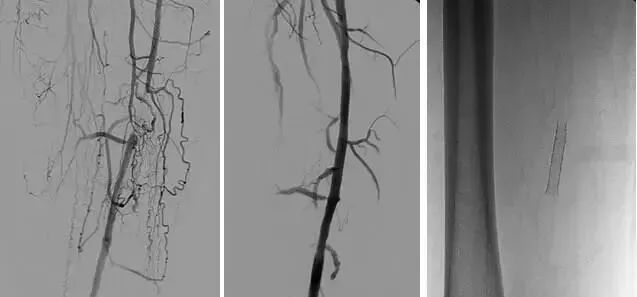

3、经皮腔内血管成形术(Percutaneous transluminal angioplasty,PTA)

60年代开始应用于动脉,使狭窄的血管扩张,70年代研制双腔气囊导管成功后,得到广泛应用,多用于髂、股、腘动脉及肾动脉。肾动脉PTA(或PTPA)多用于肾源性高血压,使狭窄肾动脉扩张,从而降低血压。PTA亦可用于冠状动脉,称为经皮腔内冠状动脉成形术(Percutaneous transluminal coronary angioplasty,PTCA),使硬化的冠状动扩张,以达到治疗冠心病的目的。PTA使用的导管为带胶囊的双腔导管,将胶囊段置于狭窄血管处,囊内注入含有造影剂的液体,加压至3~6个大气压,每次持续10—15o。加压可重复3~4次,多数能使狭窄血管达到扩张的效果。

PTA多用于动脉粥样硬化性狭窄的血管,其机理是粥样斑块受压,内膜和中层撕裂、伸展,使管腔增宽。其他原因的血管狭窄,如多发性大动脉炎,先天性血管狭窄,有时也可用PTA治疗。

(1)PTA +Stent治疗血管狭窄。

(2)溶栓+PTA和(或)Stent治疗血管狭窄。